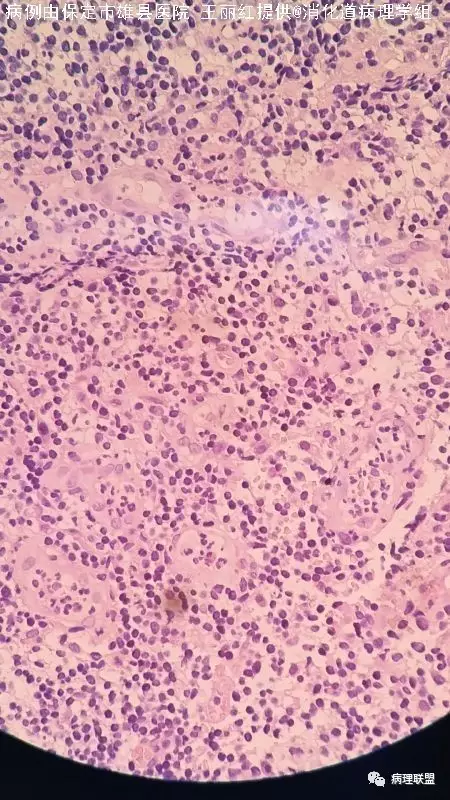

【初级医生容易犯迷糊】M/54 回盲部(炎性肉芽组织肿胀的血管内皮细胞误为异型细胞)

男性54岁回盲部(病例由保定市雄县医院王丽红提供,致谢!)

不像是肉芽肿,有异型细胞

@王丽红 炎性肉芽组织,有肿胀的血管内皮,您认为哪些细胞有异型?

@石雪迎 感谢石老师指导!那些大个的细胞是血管内皮细胞,学习了!再次感谢!